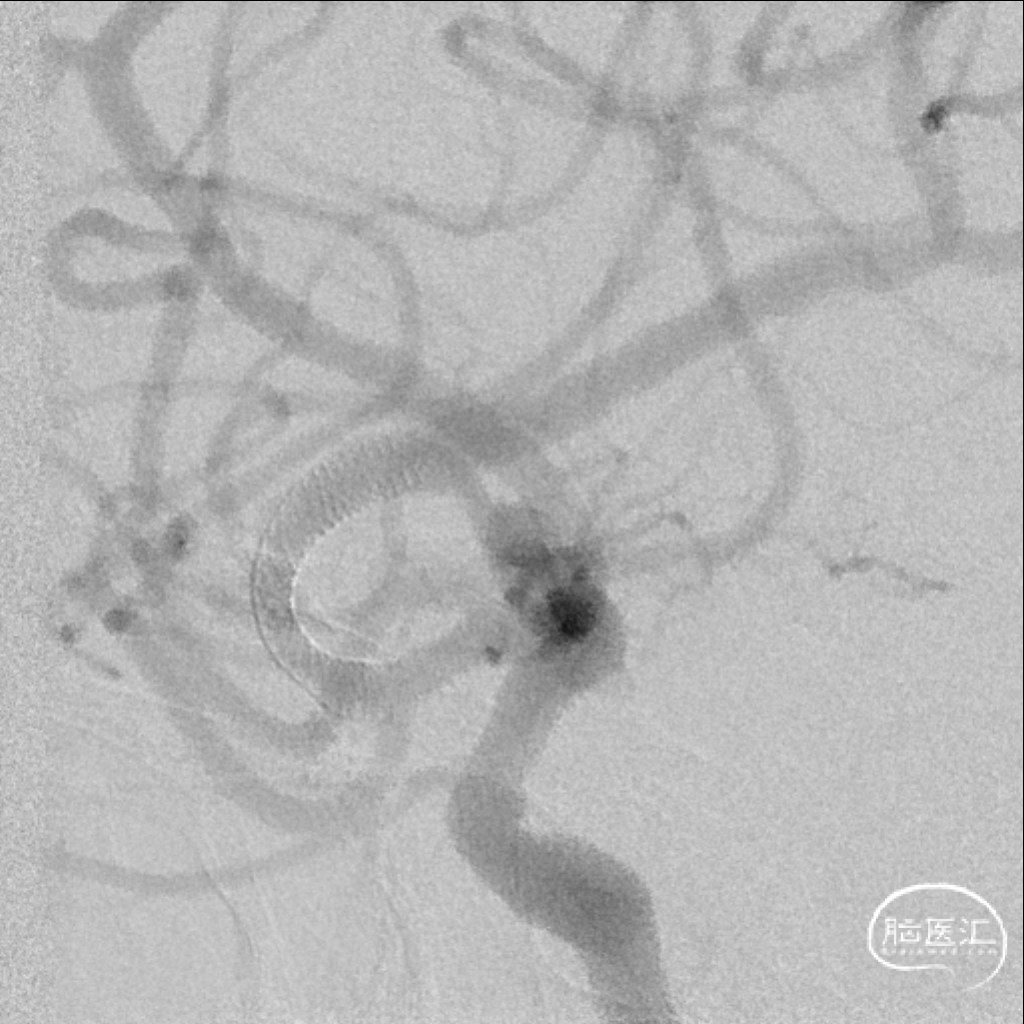

使用Tethys®中间导引导管+DCwire®微导丝通过右侧大脑中动脉M2段闭塞病变处。

微导管造影提示位于血管真腔,3*15mm 支架打开后前向血流未恢复,考虑存在动脉瘤,支架取栓操作有风险,故交换支架予以1.5*15mm 球囊扩张。

扩张后血管依然闭塞,改用2.0*15mm 球囊,扩张后提示M2段血流通畅,可见动脉瘤大小约4-5mm。

为尽快开通血管及处理动脉瘤,选择2.75*20mm 密网支架释放,并予以2.0*15mm 球囊后扩。

术后即刻影像,M2段远端血流mTICI 3级,动脉瘤内造影剂滞留。